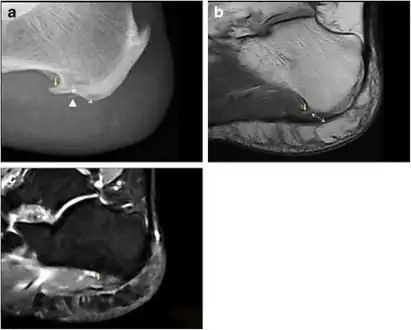

- a) Plantar calcaneal spur at the origin of intrinsic muscles of the foot b) MRI confirms the presence of a calcaneal spur c) bone marrow oedema in the calcaneal spur

- Inferior calcaneal spur